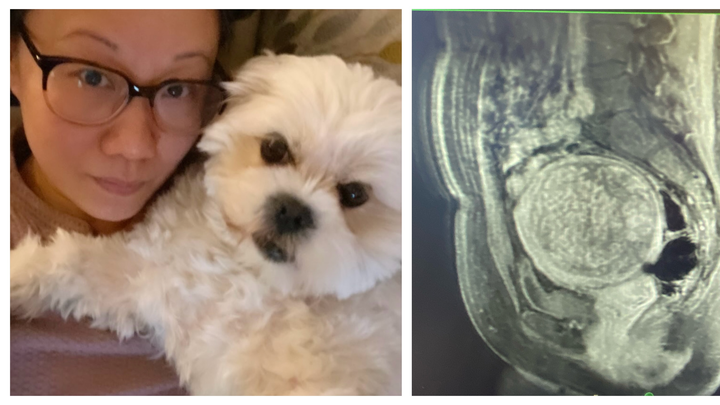

At the end of March, I will undergo a routine but complex open surgery to remove a very large (10cm) fibroid tumor from my body which I have named "Gladys", as pictured.

Yes, it's that large white circular thing that looks like a Full Moon. Gladys, the 'grapefruit', is lodged in my lower abdominal area, blocking all sorts of fun bodily functions. "Gladys" has got to GO!